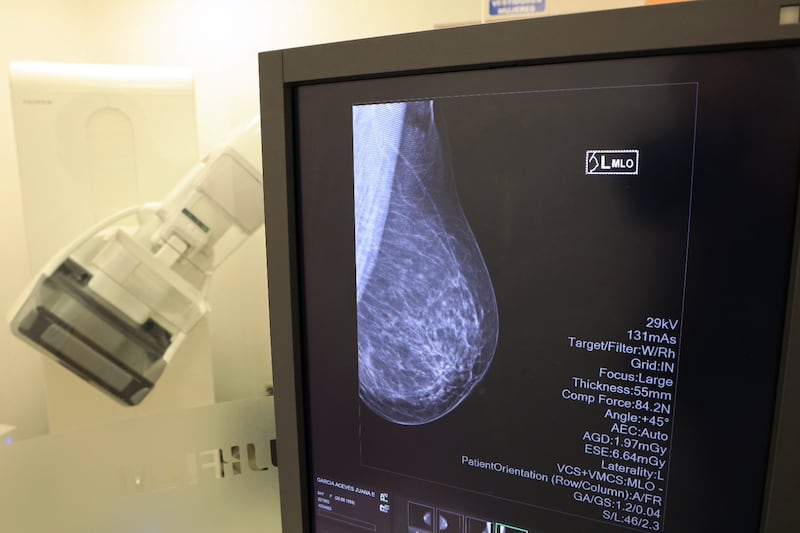

Del 06 al 31 de octubre, el hospital ofrecerá un paquete especial de mastografía, ultrasonido mamario y consulta con especialista de la Clínica de Mama por un costo preferencial de 500 pesos.

La ginecóloga del Hospitalito, Goretti Hernández Martínez, recordó que la detección oportuna puede marcar la diferencia en el tratamiento del cáncer de mama. Explicó que, a partir de los 40 años, las mujeres deben realizarse una exploración clínica anual acompañada de mastografía y ultrasonido mamario.

Las citas para mastografía y ultrasonido se programan directamente en el área de Rayos X del Hospitalito, presentando el recibo de pago. Una vez obtenidos los resultados, las pacientes pueden agendar su valoración con la Clínica de Mama, que atiende de lunes a viernes, de 08:00 am a 08:00 pm.